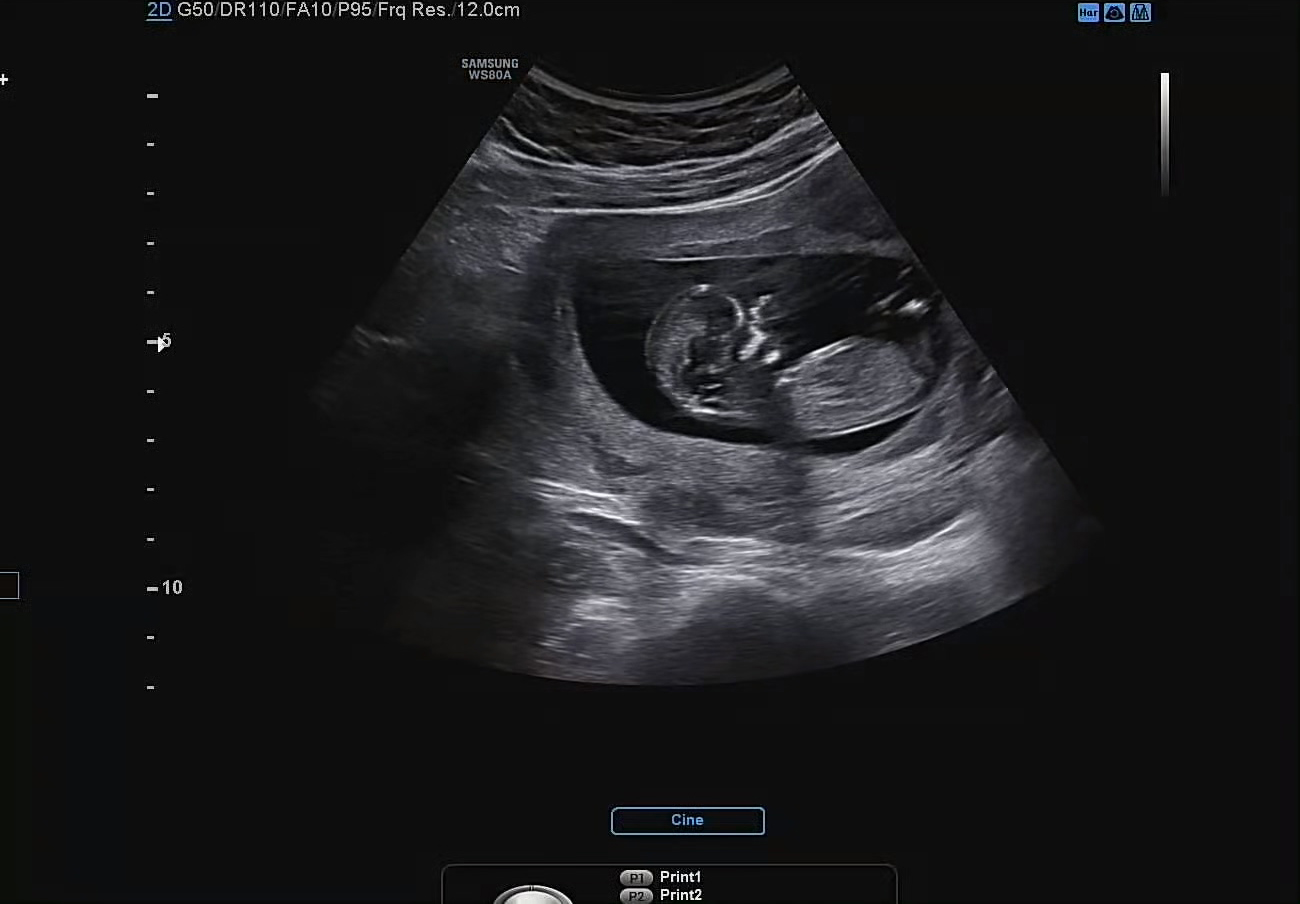

초음파 상이지만 확실히 9주 차 때보다 실루엣이 더 커지고 또렷해진 느낌이다. 특히나 얼굴에 보이는 골격이라고 해야 하나, 그런 디테일이 더 많아진 느낌적인 느낌.

까꿍이의 목 두께는 1.38mm, 코뼈도 2mm로 다행히 결과는 정상범위로 나왔다.

심박수도 9주 때와 비슷하게 160으로 잘 나왔다. 성인보다 2배 정도 빠른 심박수를 보이는 태아. 현재 6cm 정도의 작은 크기임에도 불구하고 손발과 심장이 모두 존재한다는 게 정말로 신기할 따름이다.